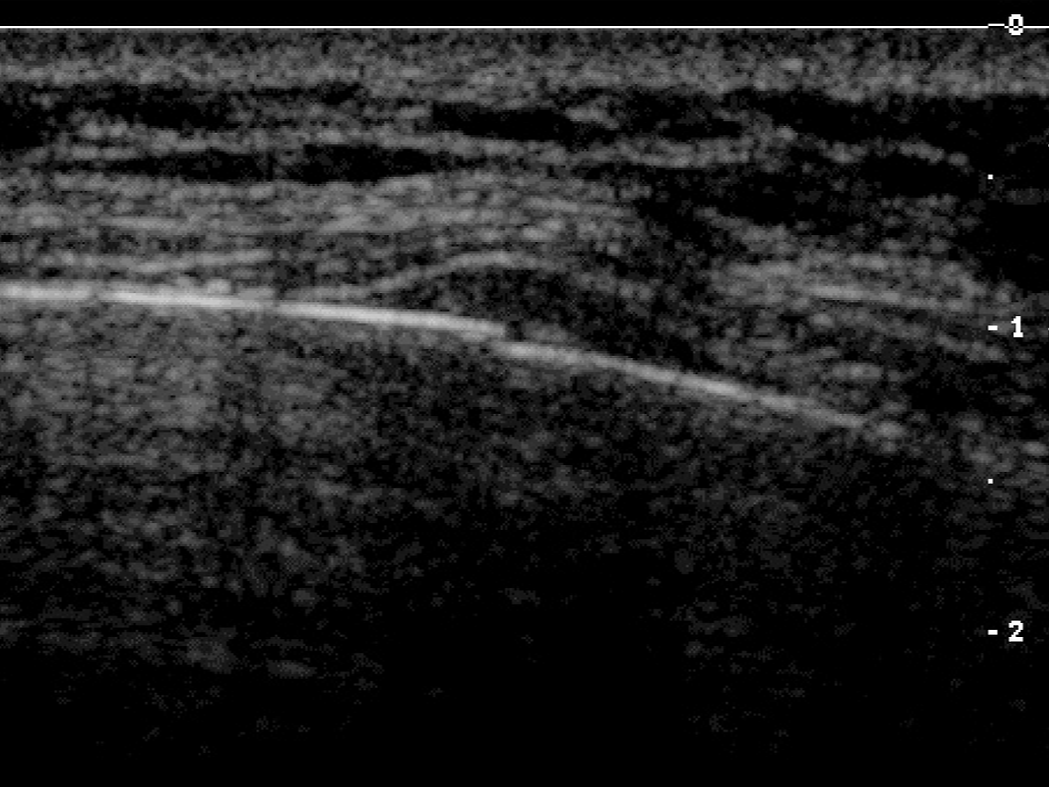

- 초음파: 폐나 다른 장기의 손상 여부를 평가할 수 있습니다. 특히 흉막 내 출혈 여부를 확인하는 데 도움을 줍니다.